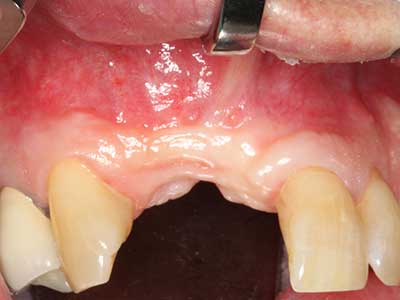

Abb. 2: Vertikaler und horizontaler seitlicher Oberkieferdefekt bei hoher Lachlinie mit Indikation zur präimplantologischen Rekonstruktion.

Abb. 3: Die basale Abtrennung des Blocks wird durch speziell abgewinkelte Aufsätze erleichtert.